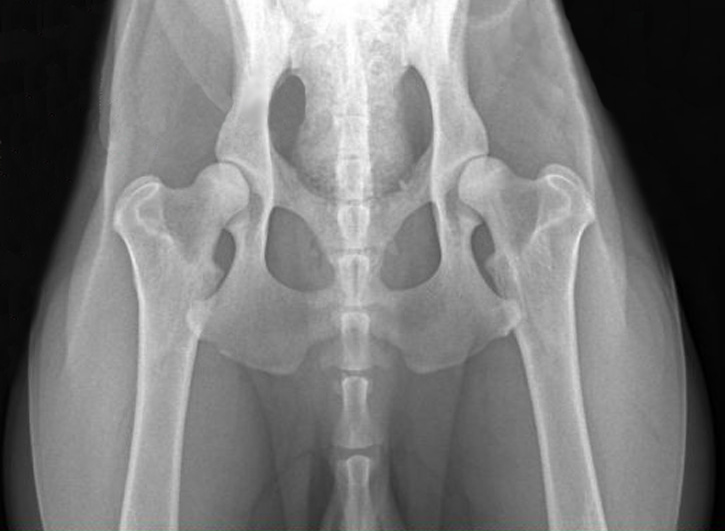

ДТБС у собак: рентгенограммы

ДТБС: степень "E" — тяжёлая форма